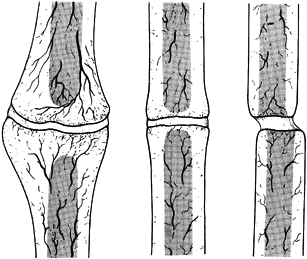

demonstrate the degree of blood supply (Fig. 26.4 and Fig. 26.5). Figure 26.4

shows vital nonunions, which have a good blood supply to both bone

fragments and demonstrate various degrees of callus formation. Figure 26.4A

is a hypertrophic, or elephant’s foot, nonunion, which is usually

caused by mechanical instability. Increasing the mechanical stability

of the fracture site will often permit these to heal. In addition, they

are usually responsive to electrical stimulation. It is important,

however, to differentiate hypertrophic nonunions from true synovial

pseudarthroses. Plain tomography or computed tomography (CT) scans with

sagittal or frontal plane reconstruction will often show a cyst in the

center of the hypertrophic nonunion. An excellent test is a technetium

bone scan, which will show increased uptake throughout the fracture

site, but the center will be cold, as seen in the pseudarthrosis of a

mid-shaft humerus fracture (Fig. 26.6). The other two types of vascular nonunions are the horse’s hoof (Fig. 26.4B) and oligotrophic nonunions (Fig. 26.4C).

These nonunions form less bone, in part because of their lack of

vitality, but this is also influenced by the bone they occur in and

their location in the bone. The oligotrophic nonunion can be difficult

to differentiate from the atrophic nonunion. This differentiation is

important as the former has a much better prognosis as a result of its

reasonably good blood supply.

Figure 26.4.

Weber and Cech’s classification of pseudarthrosis. These are the vascularized, or vital, nonunions, which have the biological potential to heal. A: Elephant’s foot hypertrophy. B: Horse’s hoof. C: Oligotrophic (often mistaken for atrophy). (From Weber BG, Cech O. Pseudarthrosis. Bern: Hans Huber, 1976.) |